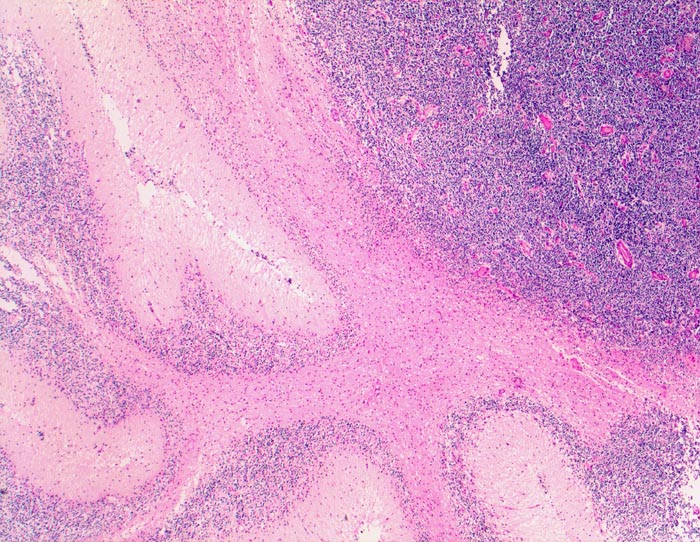

PathoPic ID 5241 - Medulloblastom

Medulloblastom

maligner Tumor

Kleinhirn

Nervensystem

Angrenzend an die Kleinhirnrinde links im Bild scharf begrenzter sehr zellreicher

Tumor.

Knabe mit Kopfschmerzen und morgendlichem Erbrechen ohne Übelkeit

Histologie

25

7

männlich